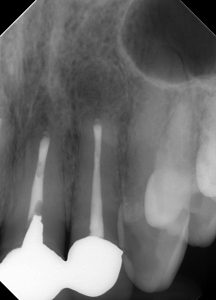

(治療直後のレントゲン、CT)

3本同時に手術を行った。

治療は1時間ちょっとで終了した。

逆根管充填をMTA→Lid Technique(BCシーラーとパテ)に変えてから、

治療時間が大幅に短くなった。

我々や患者さんにとっても、非常に大きな恩恵である。

レントゲン的に、仕上がりは問題ない。